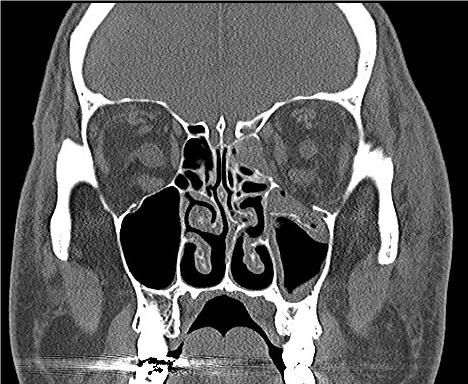

Figures: Orbital fracture.

Figure 14. Entrapment of left inferior rectus muscle from left orbital floor fracture. Patient is unable to look upward with left eye. Photo credit: Maj Brett Davies.

Figure 15. Computed tomography showing left orbital floor and medial wall fractures. Photo credit: Maj Brett Davies.